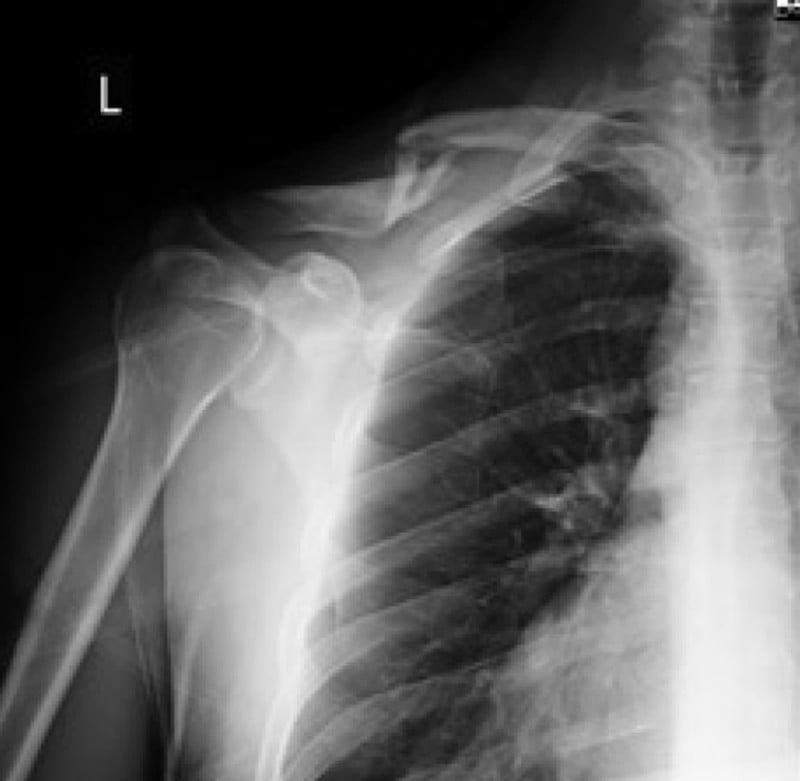

…I’m being led or carried to the bar, where I’m starting to flop onto the floor. I wasn’t even aware of what had happened. My jaw and stomach hurt, and there was a collarbone sticking out from the skin on my left shoulder. The caring people laid me on a sack chair, put ice on me, called an ambulance, and talked me into getting a shot of a painkiller.

Two days later, I had a long bruise that looked like a dark dirty coal strip across the abdomen. My jaw developed a little and I went goose-step to get a second X-ray and consultation at a private clinic in my neighborhood in Kyiv. I am a firm believer that it is better to pay a fair price and get good service than go to the low-quality municipal hospital and start hating your life afterward. At least, that’s how it works in my country.

The radiologist reshot the picture of my insides and the doctor said that I would have to secure my clavicle with a titanium plate, as the two sharp splinters of my collar bone were sticking out dangerously and could puncture a vein, so it was no longer a question of choice. All of this will cost around $1,740 (or maybe a little cheaper if you take the tests elsewhere). I must sadly note that this amount is equivalent to around four months of income for many people in the capital of my country.